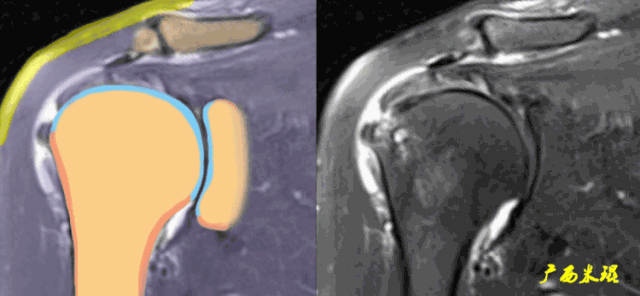

肩关节MRI检查扫描平面

(1)斜冠状位:平行于冈上肌腱长轴,主要评估冈上肌。

正常肩袖的MRI表现

各个序列肩袖均表现为均匀的低信号,是肌腱的延续。